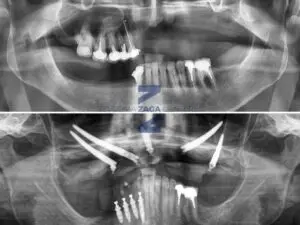

Zygomatic Implants in a Case of Severe Atrophy: ZAGA Center Paris

Full-Arch Fixed Rehabilitation with Zygomatic Implants in a Case of Severe Atrophy: A Case Report by ZAGA Center Paris Case realized by Dr. Umberto Russo,